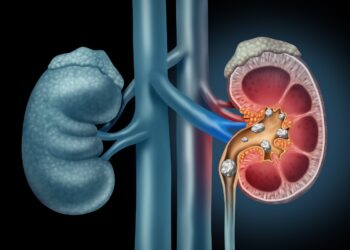

Read moreDetailsWhy Do Kidney Stones Start Forming? Most People Are Unaware Of These Facts

The problem of kidney stones is common among people of all ages. In colloquial language it is called kidney stone...